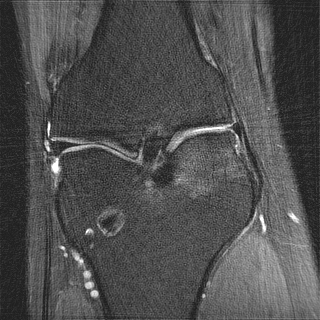

This article presents a novel undersampled magnetic resonance imaging (MRI) technique that leverages the concept of Neural Radiance Field (NeRF). With radial undersampling, the corresponding imaging problem can be reformulated into an image modeling task from sparse-view rendered data; therefore, a high dimensional MR image is obtainable from undersampled $k$-space data by taking advantage of implicit neural representation. A multi-layer perceptron, which is designed to output an image intensity from a spatial coordinate, learns the MR physics-driven rendering relation between given measurement data and desired image. Effective undersampling strategies for high-quality neural representation are investigated. The proposed method serves two benefits: (i) The learning is based fully on single undersampled $k$-space data, not a bunch of measured data and target image sets. It can be used potentially for diagnostic MR imaging, such as fetal MRI, where data acquisition is relatively rare or limited against diversity of clinical images while undersampled reconstruction is highly demanded. (ii) A reconstructed MR image is a scan-specific representation highly adaptive to the given $k$-space measurement. Numerous experiments validate the feasibility and capability of the proposed approach.